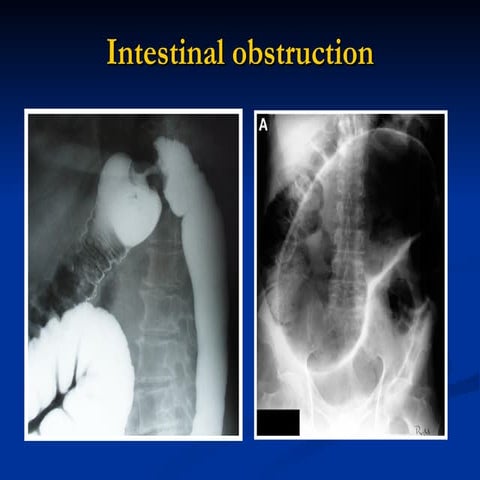

 Results in partial or complete obstruction

 May also compromise bowel circulation

resulting in ischemia

large, dilated loop of large bowel with an inverted U-shape

with walls between two volvulated loops pointing from LLQ toward RUQ;

same patient with decompressed sigmoid volvulus following insertion of rectal tube